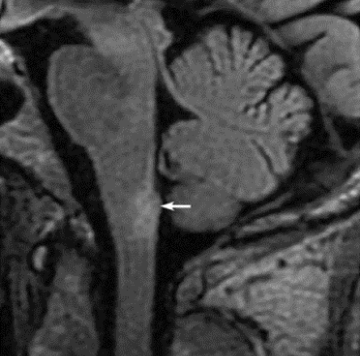

- Продольно-распространенный ПМ (ПРПМ). Он охватывает более 3 смежных позвоночных сегментов и преимущественно включает центральную часть спинного мозга (серое вещество).

Острый миелит при ЗСОНМ МРТ в режиме Т2. Типичный очаг ПРПМ, захватывающий большую часть грудного отдела спинного мозга (белые стрелки)1